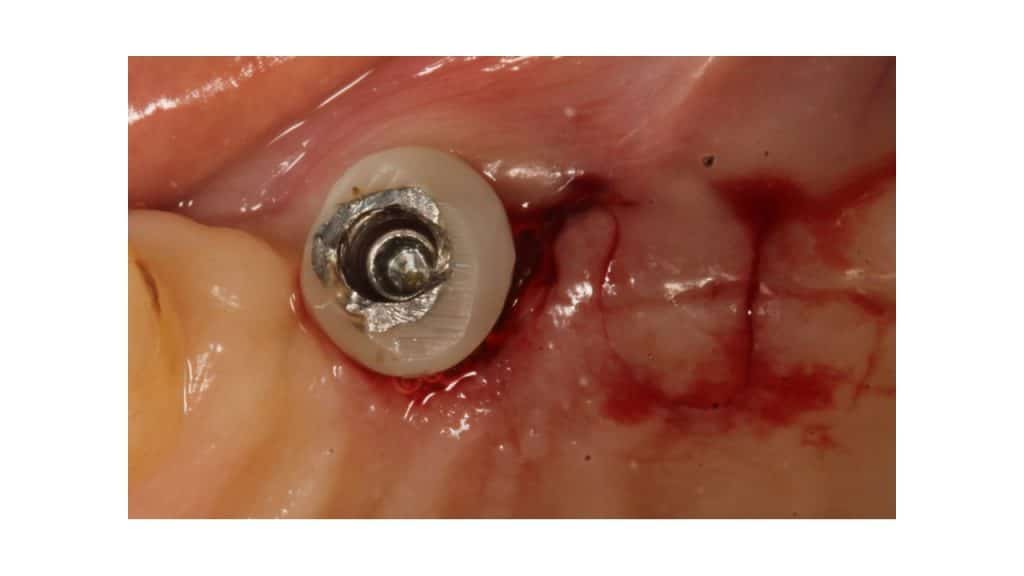

Conelog Progressive Line fixture 4.3X7 was placed along with a Customized Healing abutment to create a wider emergence & prevent fixture to be inadvertently pushed into the sinus. The fixture has crestal anchorage thread design which allows excellent primary stability even in minimally available residual ridge dimensions in the posterior maxillae.

Covers screws connected with site 23,24 for closed healing & 26 with wide emergence custom healing abutment

Optimal emergence profiles obtained at 23,24 & 26